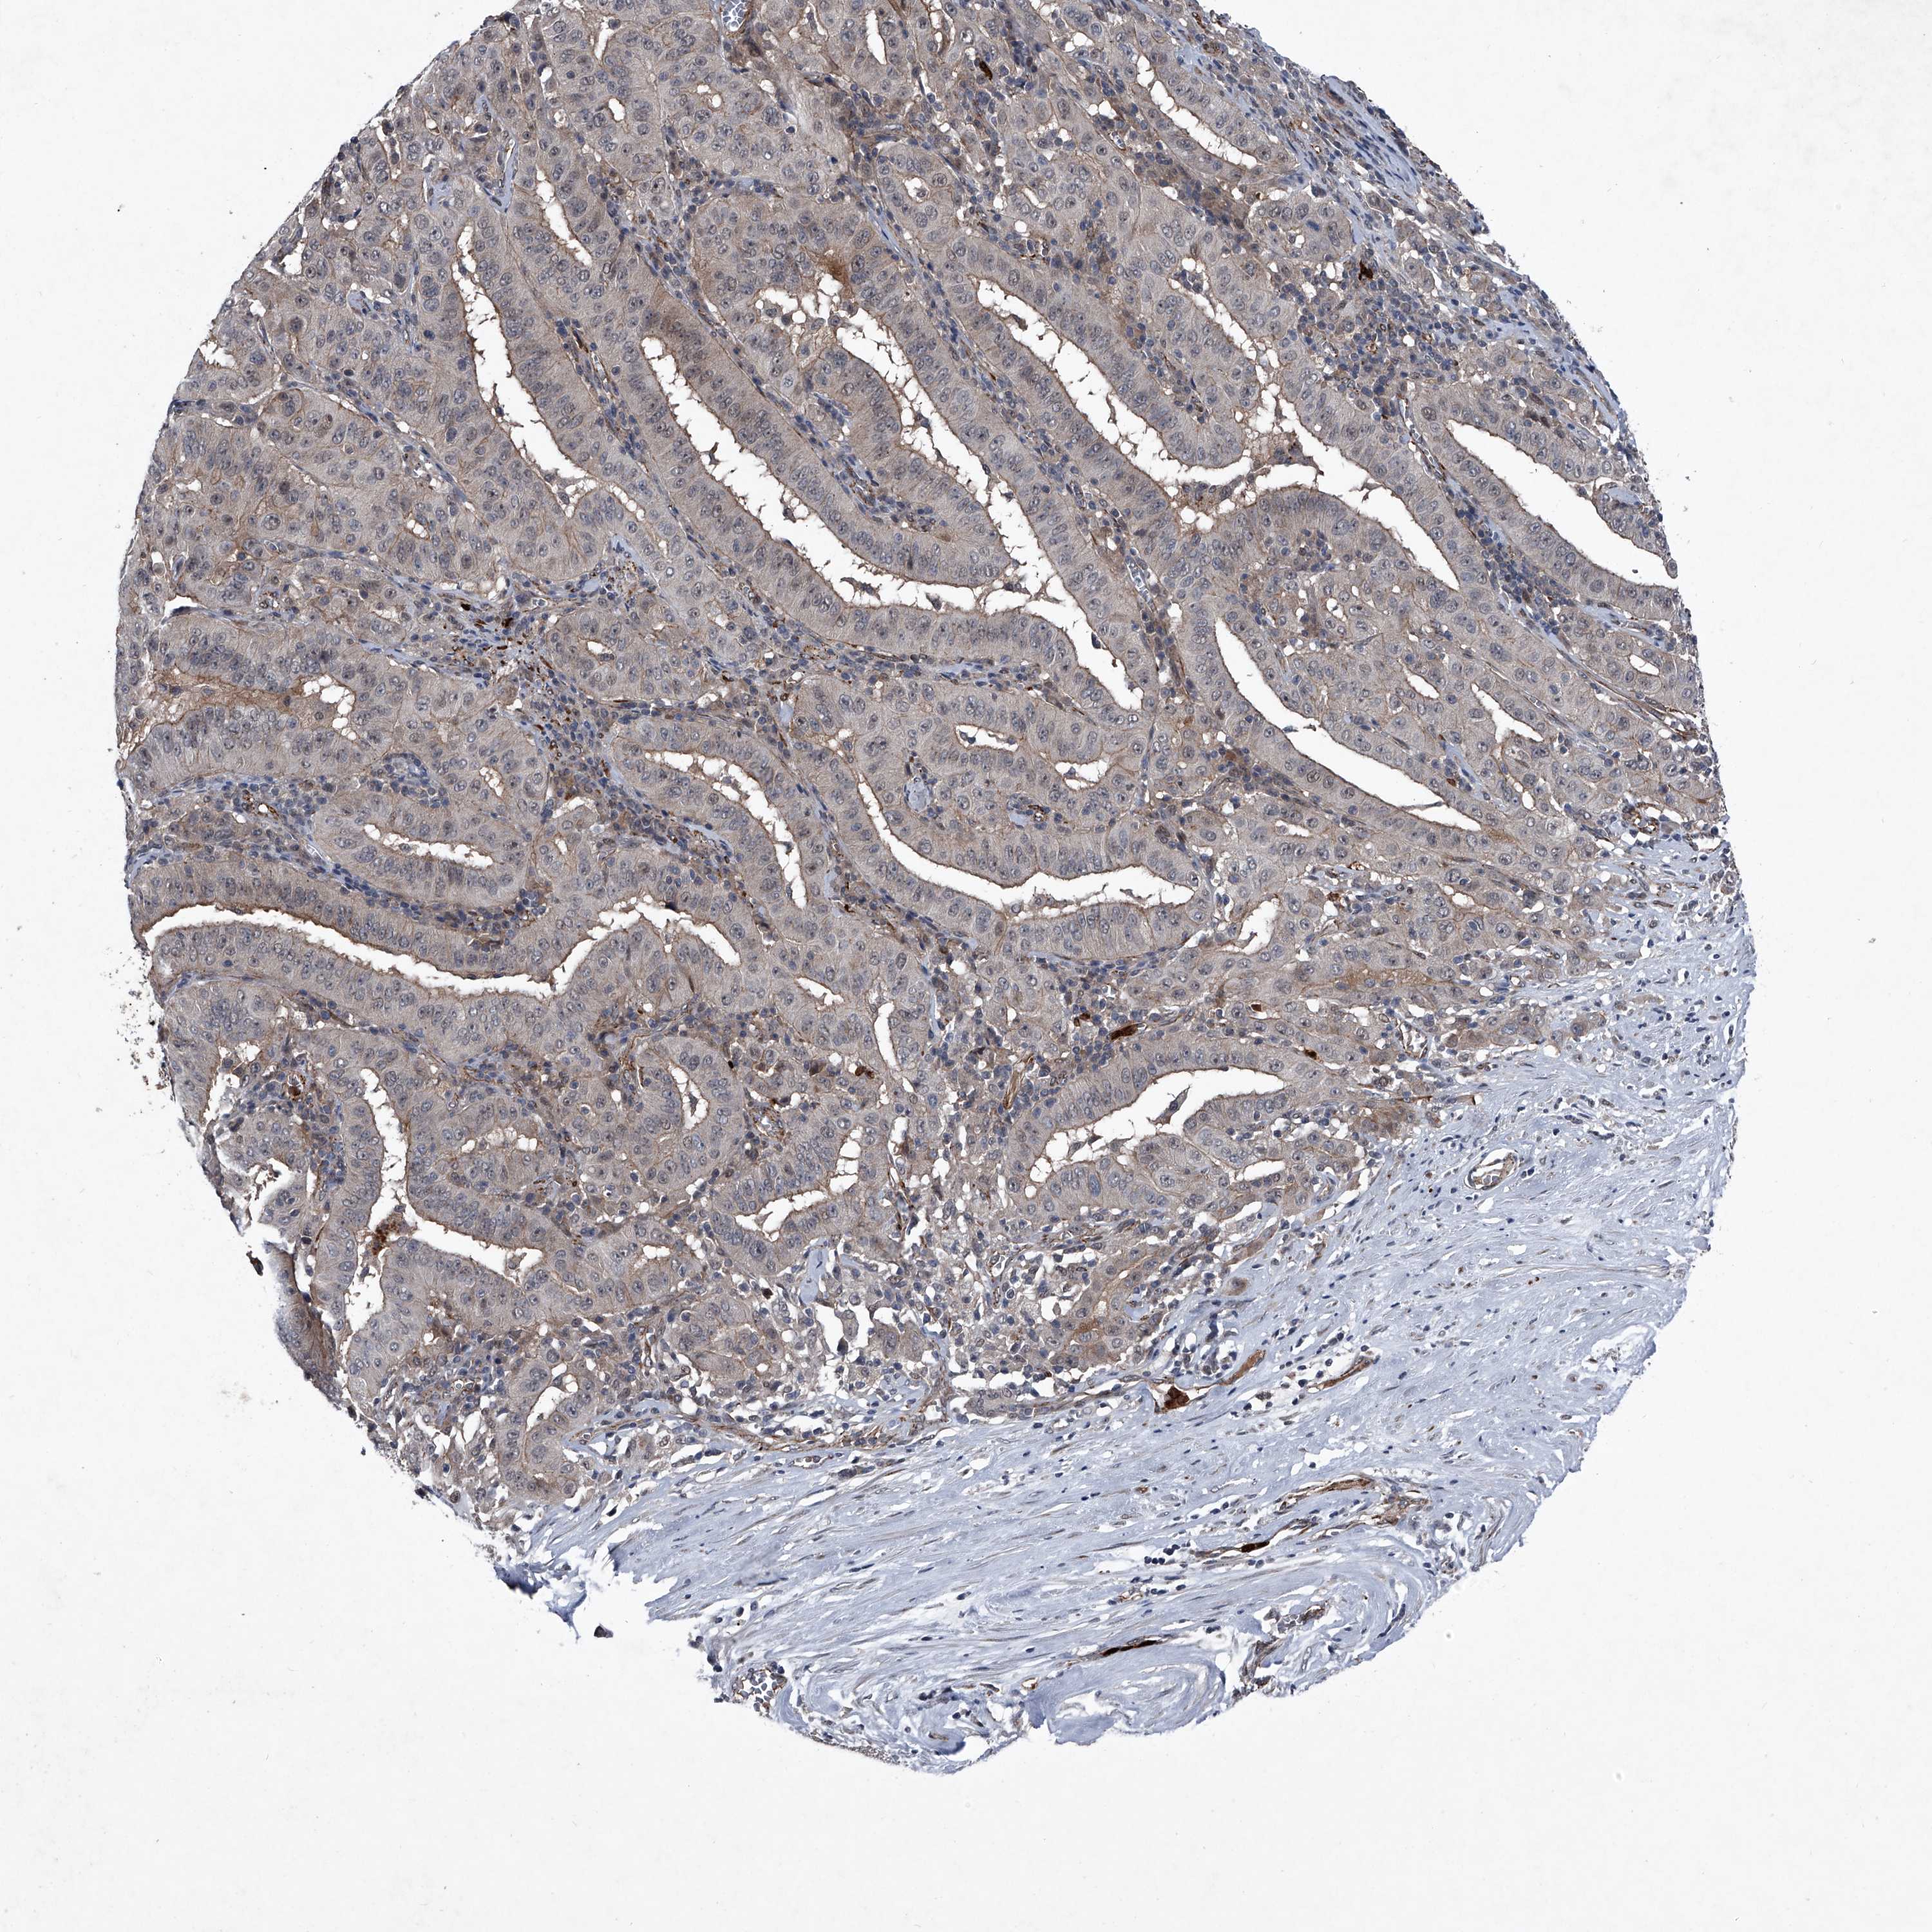

PANCREATIC CANCER - Protein expressioni

A mouse-over function shows sample information and annotation data. Click on an image to view it in a full screen mode. Samples can be filtered based on level of antibody staining by selecting one or several of the following categories: high, medium, low and not detected. The assay and annotation is described here.

Note that samples used for immunohistochemistry by the Human Protein Atlas do not correspond to samples in the TCGA dataset.

Antibody stainingi

Antibody staining in the annotated cell types in the current human tissue is reported as not detected, low, medium, or high, based on conventional immunohistochemistry profiling in selected tissues. This score is based on the combination of the staining intensity and fraction of stained cells.

Each image is clickable and will lead to virtual microscopy that enables deeper exploration of all samples and also displays staining intensity scores, fraction scores and subcellular localization as well as patient and tissue information for each sample.

Antibody HPA029091

Antibody HPA029092

Staining

High

Medium

Low

Not detected

Intensity

Strong

Moderate

Weak

Negative

Quantity

>75%

75%-25%

<25%

None

Location

Nuclear

Cytoplasmic/membranous

Cytoplasmic/membranous,nuclear

Adenocarcinoma, NOS